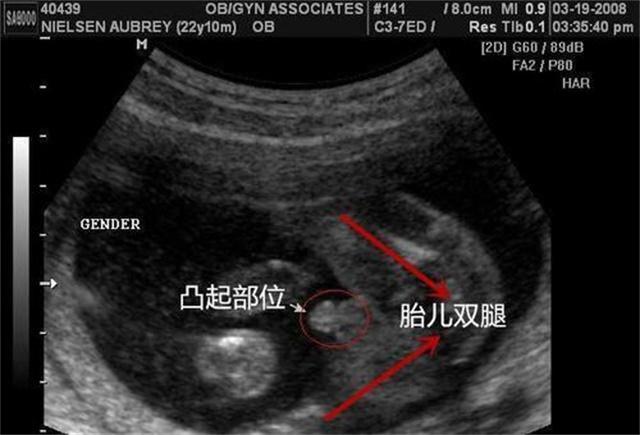

この挑戦を前に、北京中医薬大学の楊振先生と呂志来先生がマイクロブログを通じてバトルに参加することを表明した。現在、双方は挑戦の具体的なプログラムについて協議しているとされ、当初は32人の出産適齢期の女性がテストに参加する予定で、挑戦者と参加者の間には布のカーテンがあり、テストでは脈の診断結果のみに基づいて参加者の妊娠を判断する。

脈拍は妊娠を診断することができるので、現在クリニックで適用されていますか?鄧聡の紹介によると、"健康な女性が妊娠しているだけで、診断が難しく、妊娠週数が増えるにつれて、脈拍はますます明らかになります。一般的に3ヶ月以上になると、脈が滑りやすくなります。"と紹介した。鄧聡は、現代医学の妊娠診断の使用は確かにはるかに安全であることを指摘し、純粋に脈拍は確かに少し一方的であり、その精度は統計されていない。

鄧博はまた、中国の病院であろうと西洋の病院であろうと、臨床基準における妊娠の診断において、「脈拍妊娠検査の診断」がないことは確かであり、妊娠診断のゴールドスタンダードは尿検査、血液検査、超音波検査の3つであると述べた。

そのため、今ほど多くの検査がなかった古代では、脈診が比較的正確な診断方法でした。現代では、尿検査、血液検査、超音波検査など、妊娠を診断する手段はたくさんあり、簡単な予備検査として使用し、最終的にはより正確な方法で判断することができます。この時、伝統医学の脈診は、早期発見の予備的な手段の一つとして使用することができ、最終的な確認には超音波検査を併用します。

さらに、誤診を避けるために、血中のヒト絨毛性ゴナドトロピンの濃度を調べるだけでなく、Bモード超音波検査、超音波ドップラー検査など、他の補完的な検査を行うこともある。